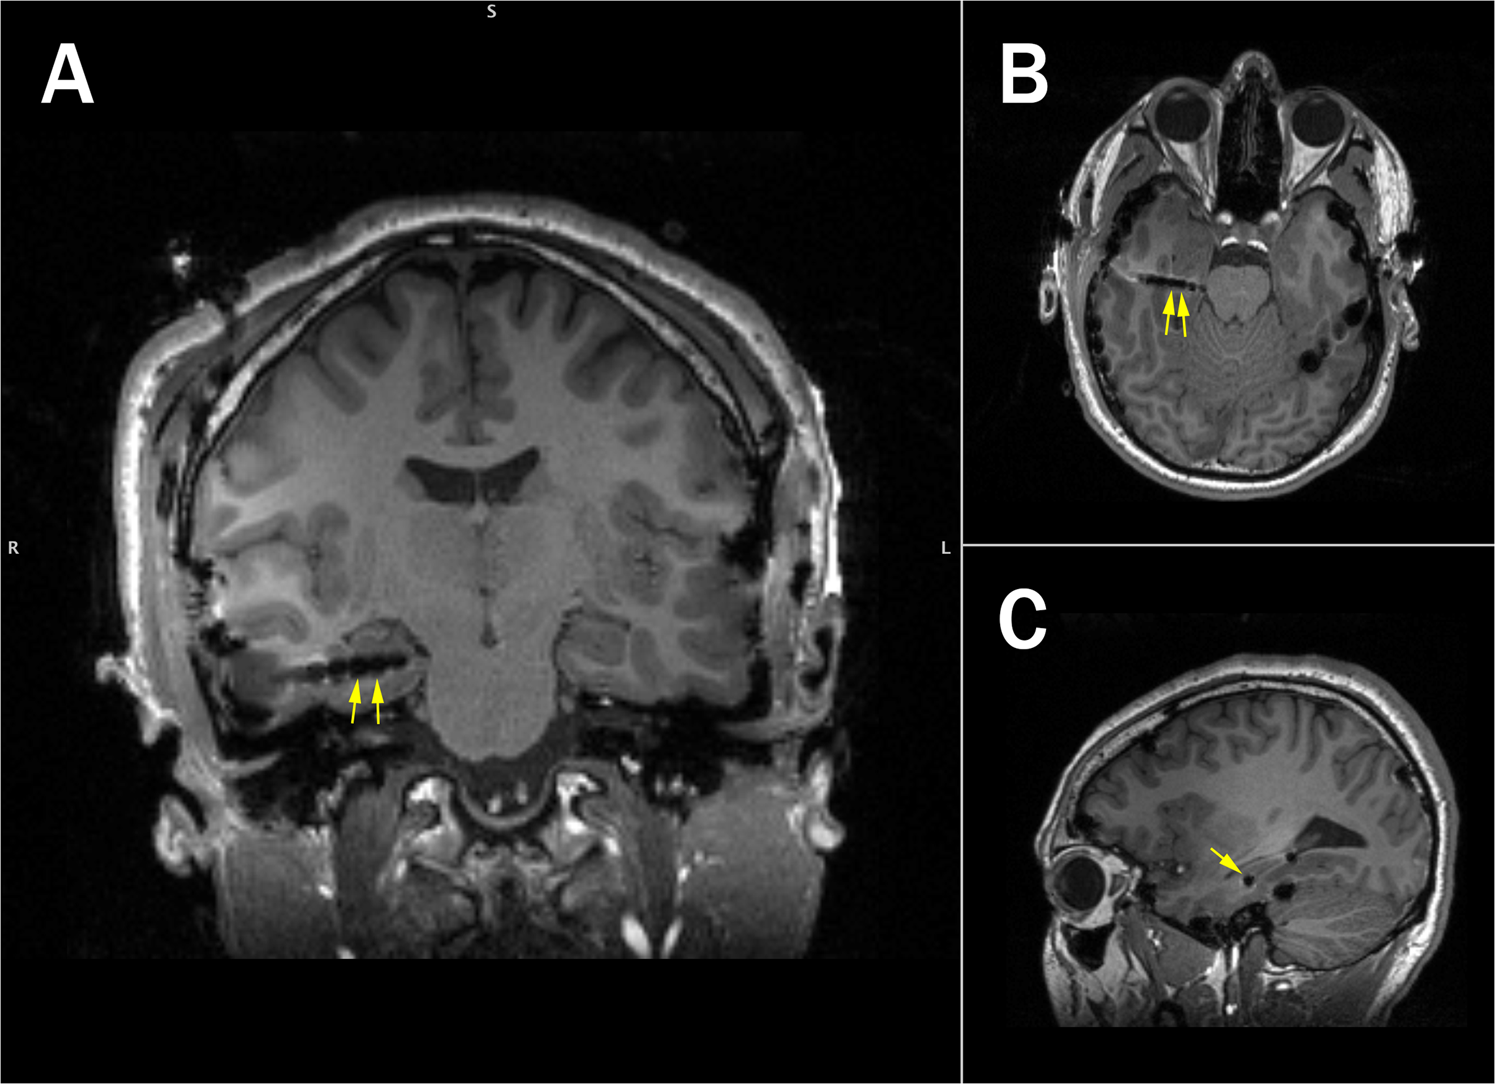

Electrode localization for an example surgical patient (S2). Location of selected electrodes is indicated with the yellow arrows (Right Anterior Temporal 03/04, A: Coronal, B: Axial, C: Sagittal).